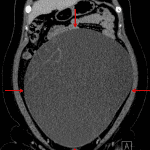

Age: 24

Sex: Female

Indication: Abdominal distension and pain

Findings

- Lower chest

- Minimal dependent atelectasis

- Abdomen/Pelvis

- Large, predominantly cystic mass measuring 30 x 30 x 15 cm filling the pelvis and much of the abdomen, which appears to arise from the left ovary

- Several thin internal septations in the upper right aspect of the mass

- The right ovary is separate from this mass with several intraovarian cysts measuring up to 4.8 cm

- Heterogeneous enhancement of the uterus

- No bowel obstruction or hydronephrosis

- Small volume free fluid layering in the anatomic pelvis

Diagnosis

- Cystic ovarian neoplasm (mucinous cystadenoma)

Large predominantly cystic mass appearing to arise from the left ovary with extensive mass effect but no evidence of bowel obstruction or hydronephrosis. The primary differential consideration is a cystic ovarian neoplasm. Recommend gynecology assessment and consideration of MRI for further evaluation.

Cystic right ovarian lesions which can also be further evaluated with MRI.